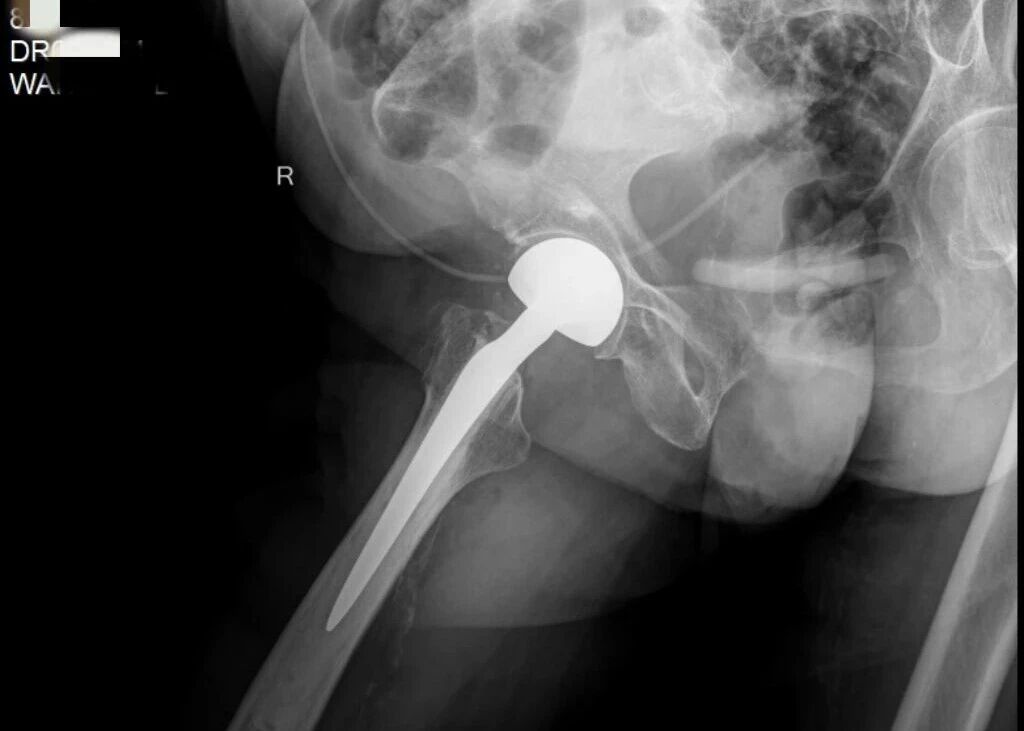

(▲术后)

骨伤儿科主任肖放军带领团队在多学科的配合下手术顺利完成。

手术成功只是第一步,术后,科室启动快速康复。

以“零压疮、零肺炎、零血栓”的目标,团队筑起了坚实的安全防线,全程的疼痛管理确保奶奶舒适,术后第一天,王奶奶就在护士的指导下下床行走了。